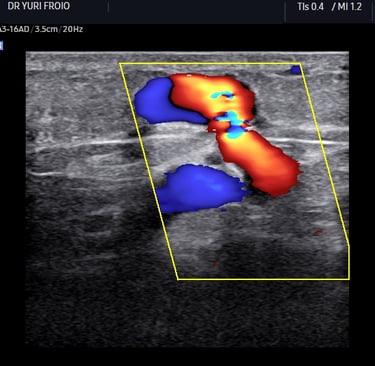

Ultrassom: ondas sonoras criam imagens das veias.

Doppler: identifica a direção e velocidade do sangue (cores no aparelho indicam fluxo normal ou alterado).

O Doppler emite sons e mostra cores no monitor (fluxo sanguíneo).

O Que o Doppler Revela Sobre Suas Varizes?

Mapa Venoso: localização exata das veias doentes.

Grau de Refluxo: se há sangue retornando (principal causa de varizes).

Coágulos (trombose): risco de complicações graves.

Função Valvar: se as válvulas das veias estão funcionando.